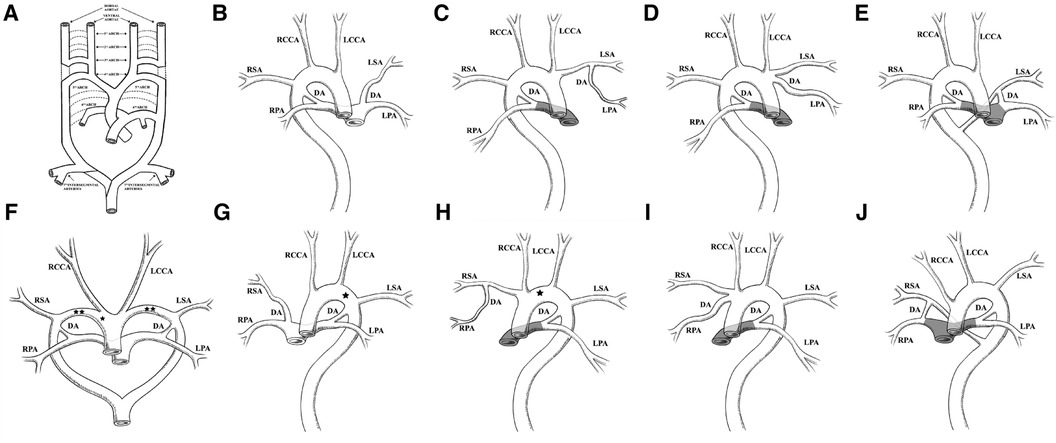

Based on the findings of this case, we reviewed all literature works on BDA and summarized 40 cases of BDA in 25 articles over the last few decades. Some of the cases in the literature did not provide basic information and imaging findings of the anatomical features of specific cases; therefore, they were not included in the summary in Table 1 (31). The characteristics of these cases are that at least one side of the DA is not directly connected to the DAo, and they are all reported during the fetal or infant periods. Figure 3 can be used to understand the combination forms of these anomalies.

In Table 1, 41 cases of BDA were included (including the cases in our study). Only 11 cases were reported during the fetal period (26.8%, 11/41). The age range of the other reported cases is from 1 day to 18 months after birth. Among the 41 cases, 26 (63.4%, 26/41) had congenital heart disease (CHD), 13 (31.7%, 26/41) did not have CHD, and the presence of CHD was not mentioned in the others. Among the 26 cases of CHD, there were 9 cases of PA, 7 cases of IAA, 6 cases of TGA, 4 cases of AVSD, 3 cases of PTA, and 3 cases of SV. These cases of PA were all reported in the infant period. In addition, in cases where birth outcomes could be followed up, DA closure occurred in 4 cases of RAA without CHD; however, in the other 17 cases, the DA was not closed, and all cases were combined with CHD. Among them were seven cases of PA, indicating that the DA provides the blood supply to both lungs. Because many studies have only reported the cardiac manifestations, the summary of extracardiac anomalies is not comprehensive. Heterotaxy syndrome (HTX) has the highest incidence, with three cases reported, which is similar to previous studies findings (9, 31). HTX is a laterality defect. In recent years, many scholars believe that TGA and AVSD are also laterality defects. In addition, most HTX patients also have PA (32). Our summary in Table 1 found that the highest incidence of CHD in BDA is PA, TGA, AVSD, etc. In addition, BDA always appears heterotopic on the opposite side of the aortic arch. The above clues indicate that TGA with BDA could further support the hypothesis of TGA as a form of latency defect.